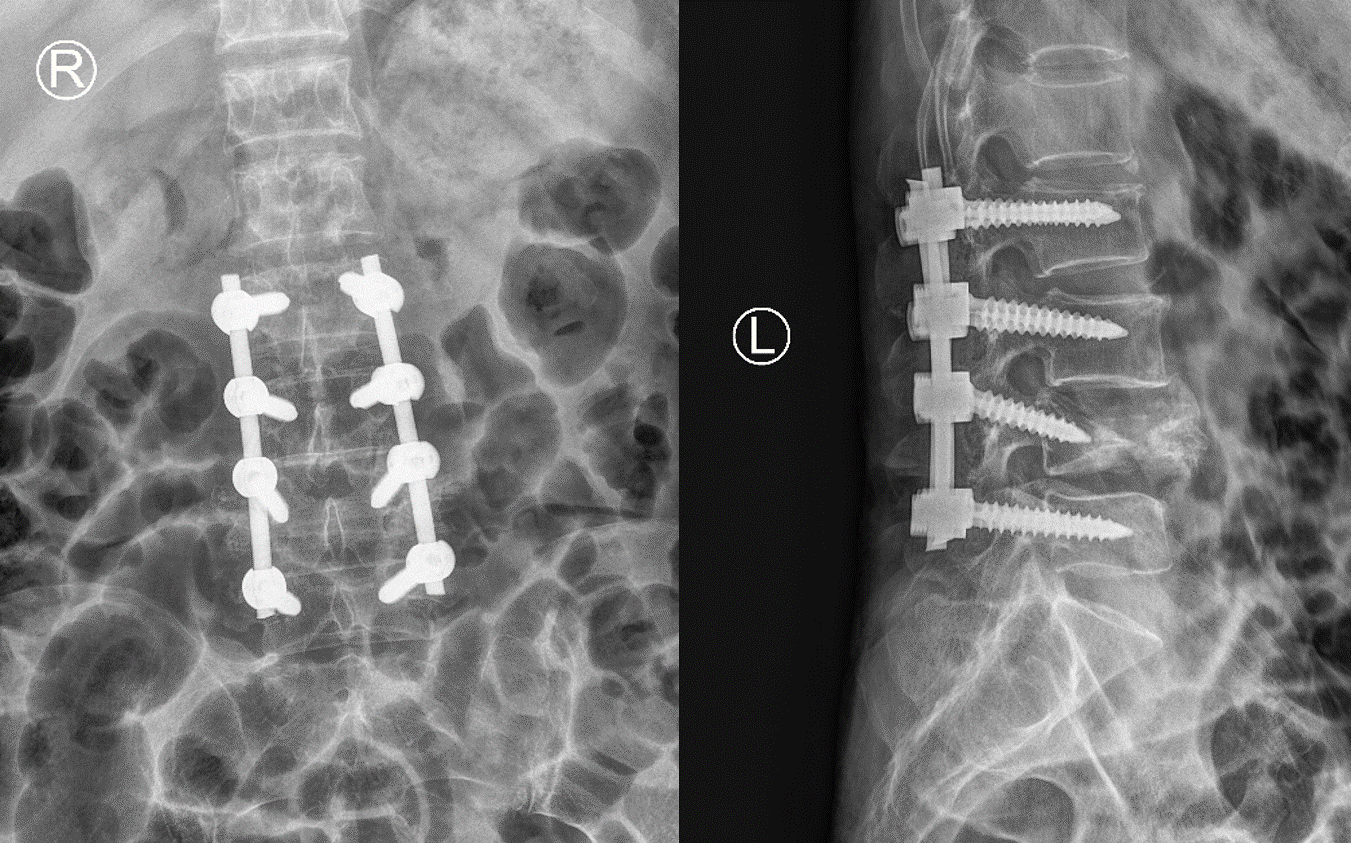

L4椎体高度恢复,脱位情况得到极大改善

患者腰椎序列恢复满意,稳定性得以重建